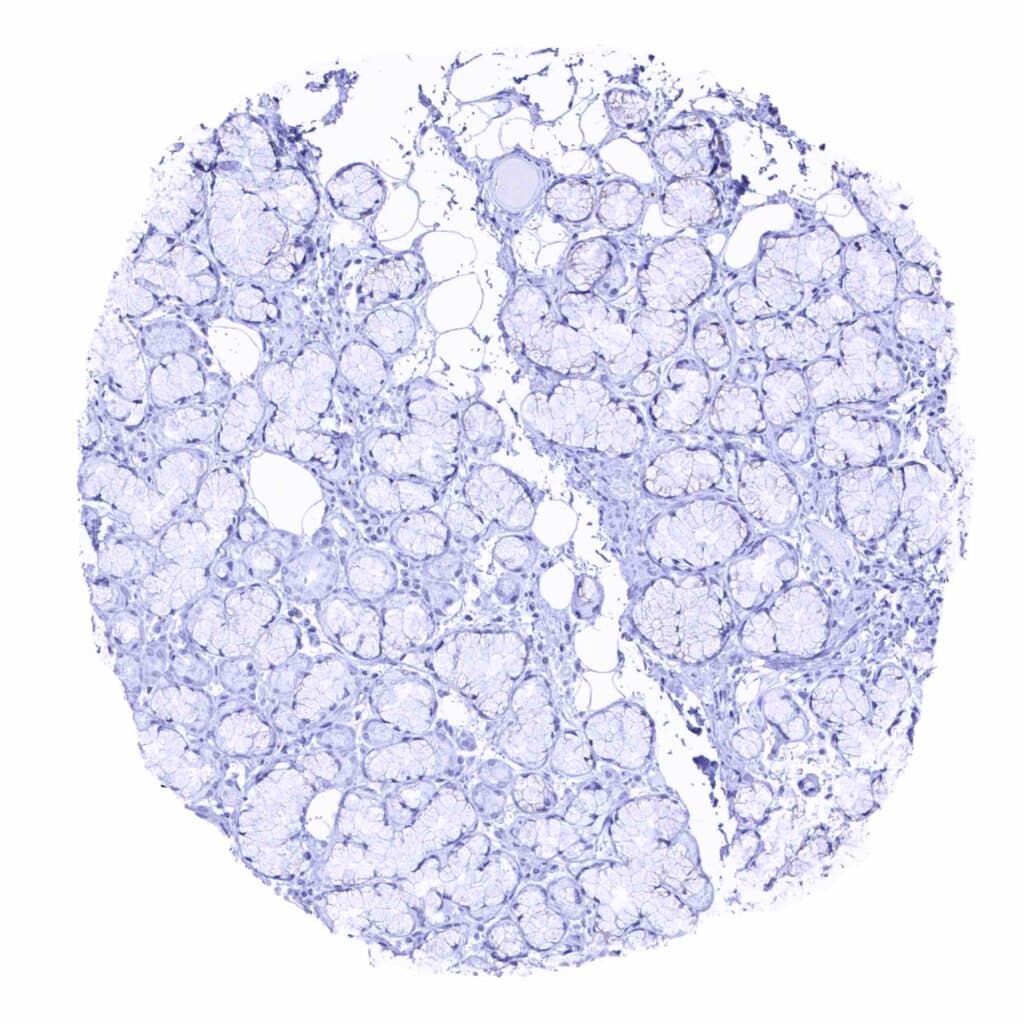

Prostate – Intense granular, cytoplasmic prostein staining of luminal cells of the prostate (prostein immunohistochemistry)

Prostate – Luminal epithelial cells of the prostate show a strong granular, perinuclear cytoplasmic prostein staining (prostein immunohistochemistry)

Prostate – Strong, granular, perinuclear cytoplasmic prostein staining of luminal cells of the prostate (prostein immunohistochemistry)